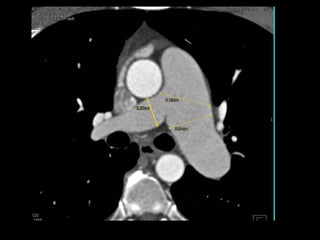

Tomografia computadorizada

Angiotomografia dos vasos pulmonares com TCMD

e reconstruções com filtro de alta resolução;

Mede-se o tronco da pulmonar próximo à sua

bifurcação e lateralmente à aorta ascendente;

Em adultos: até 29 mm;

Sensibilidade: 69-87%;

Especificidade: 89-100%.

Um diâmetro da artéria pulmonar > aorta

ascendente: sensibilidade de 70% e especificidade

de 92% no diagnóstico de HAP;

Achados parenquimatosos: dependem da etiologia

e mecanismo da hipertensão:

Perfusão em mosaico, vidro fosco, espessamento

septal e nódulos centrolobulares.

Derrame ou espessamento pleural, e, em pacientes

com HAP grave, pequeno derrame pericárdico.